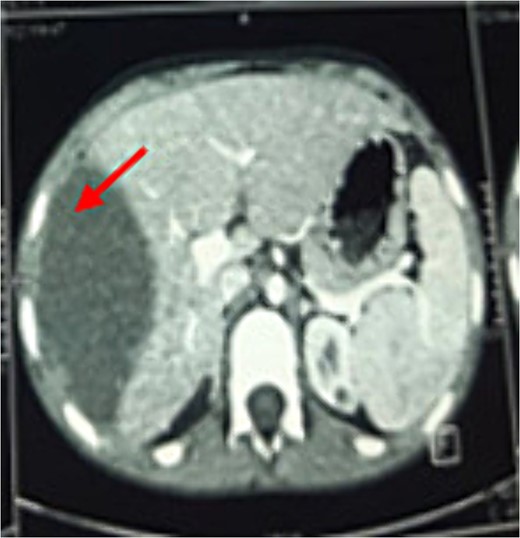

A chest X-ray demonstrated right hemi-diaphragmatic elevation. Given this finding, a computed tomography scan (CT) of the chest and abdomen was performed for further evaluation. The CT report concluded the presence of a hydatid cyst originating from the hepatic dome with a suspected intrathoracic extension (Figs 1 and 2). Serological testing for echinococcosis was positive.

Coronal chest CT view 11 × 4 cm2 hydatid cyst that seems arising from the liver with possible intrathoracic rupture.